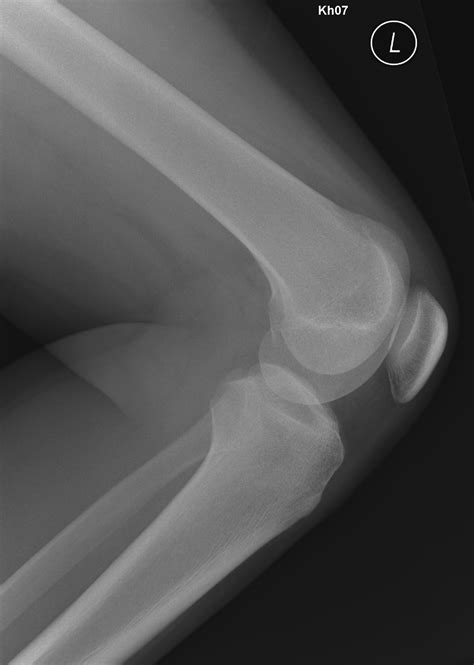

The primary purpose of an Osgood Schlatter X ray is not necessarily to "diagnose" the condition, as that is primarily a clinical diagnosis, but rather to look for specific findings that confirm the stress at the insertion point of the patellar tendon. When reviewing these images, medical professionals look for:

• Soft tissue swelling: Visible inflammation around the patellar tendon.

• Fragmentation: In more chronic or severe cases, the X-ray may show small bony fragments pulling away from the tibial tubercle.

• Irregularity: The surface of the bone may appear rough or jagged rather than smooth.

• Rule-out conditions: It is crucial to ensure the pain is not caused by bone tumors, fractures, or infections, which may present similarly.

If your doctor requests an Osgood Schlatter X ray, you should not be concerned. It is a quick, painless, and low-radiation diagnostic procedure. Typically, the technician will take images from a few different angles, most notably a lateral (side) view of the knee, to get a clear picture of the tibial tubercle.